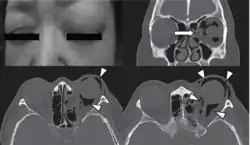

![]() | |

| Woman with preorbital swelling in orbital emphysema shown in CT scans | |

Physical examination

Physical examination of the eyelid can be done by the palpation for the pathognomonic cracking, crepitation,[11] and tense tissue[35] on the upper and lower eyelids. The findings of the examination are supported with the medical history of the patient and confirmed with orbital CT.[6]

Computed tomography (CT)

Computed tomography is effective and sensitive in the diagnosis of orbital emphysema,[3][37] as it can confirm the anatomical location and size of air, bony defects, indentation of the eyeball, and the condition of the optic nerve, as well as the presence of any extraocular muscle entrapment and herniation of preorbital fat into the sinus cavities.[3][15][38] The location of the orbital emphysema is present near the site of the fracture.[1][3] The scans are usually taken along the transverse plane. Transverse images allow the evaluation of fractures in medial and lateral orbital walls. By reformatting these transverse images or taking coronal images, the examination of orbital floor and roof is permitted. Helical scanning is preferred as it has a lower imaging time and radiation dose comparing to conventional scanning, especially when reforming transverse helical scans into coronal images.[3] The staging of orbital emphysema can then be determined with visual acuity examination and ophthalmoscopy.[6] A disadvantage of using a CT scan is that when detecting air after orbital trauma, the presence of a wooden foreign object can give a false positive result of orbital emphysema. The wooden object can mimic the presence of orbital emphysema. Therefore, patients’ medical history is crucial in making the correct diagnosis.[3]